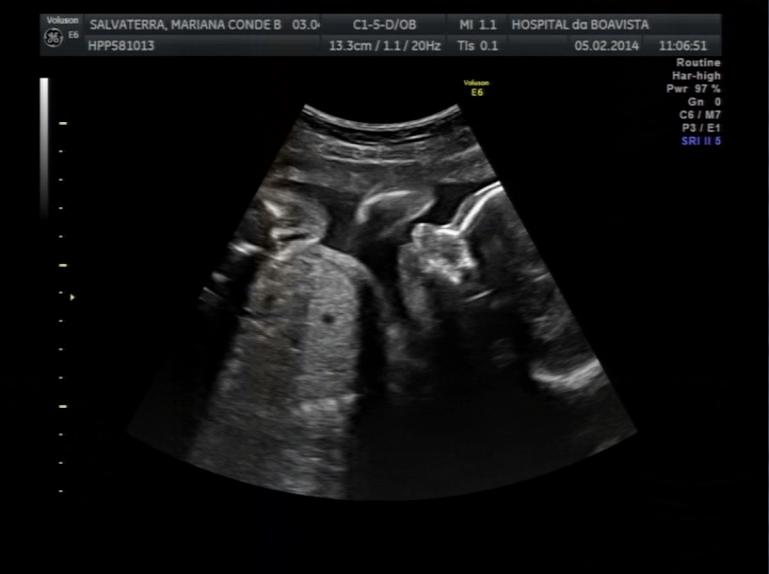

Nova eco, será desta?

Temos uma nova ecografia amanhã, deixa-nos ver se és menino ou menina, deixas?

Os Papás querem muito saber para acabar de escolher o teu nome!

Deixa ver, sim?

E não foi desta!!!

Que teimoso que nos saíste!!! Ou deverei dizer teimosa?!

Parece que és menina mas sem certezas... Vamos tentar fazer nova eco ainda esta semana a ver se temos certeza do que és para anunciarmos o teu nome!